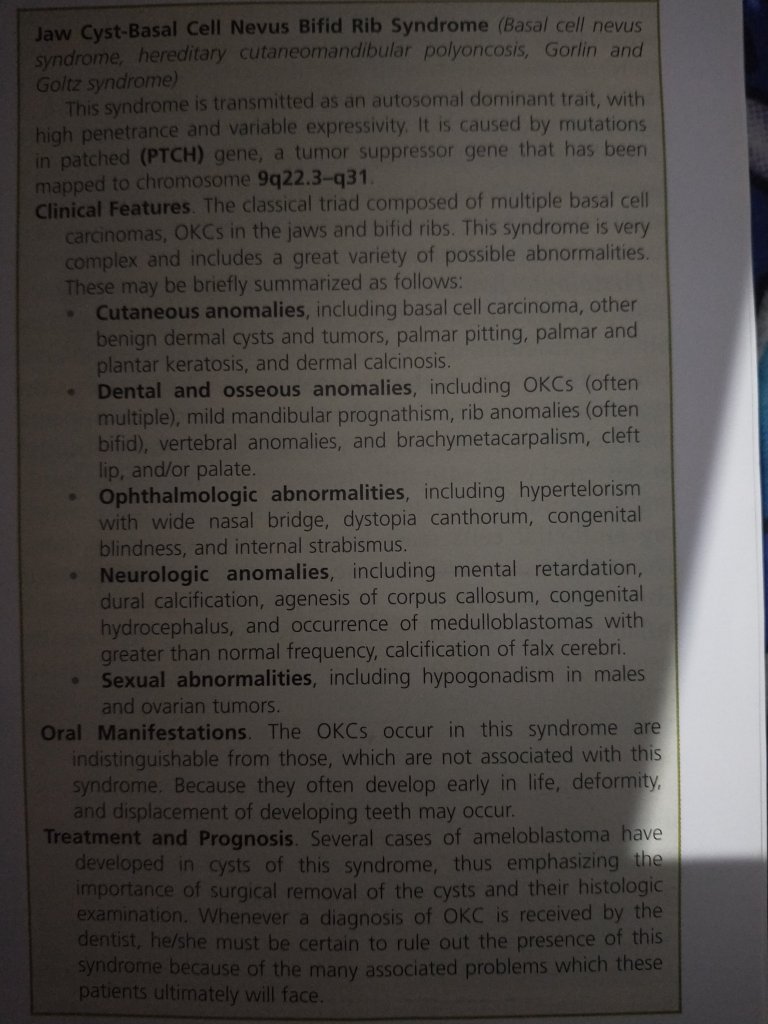

- Patients with nevoid basal cell carcinoma syndrome (Gorlin- Goltz syndrome) have a particular tendency to form multiple keratocysts with other manifestations in different parts of the body (Multiple basal-cell carcinomas of the skin, rib and vertebrae anomalies, intracranial calcifications, frontal bossing, hypertelorism , and mandibular prognathism .palmar and plantar pitting ).

3. Some cysts may be left behind in cases of Gorlin Gotz syndrome.

It is also essential that patients with an OKC, especially if multiple, be evaluated medically to rule out the possibility of the jaw cyst-basal cell nevus-bifid rib syndrome .